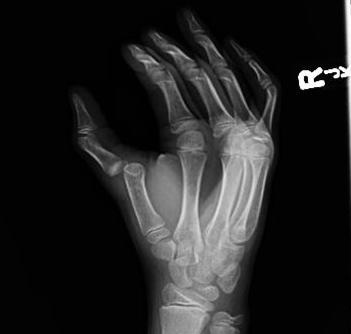

The Bennett fracture, Rolando fracture, and skier’s thumb all present with pincer grasp weakness. However, the injuries may be differentiated by the location of tenderness. Skier’s thumb (UCL tear) is characterized by point tenderness and instability at the thumb MCP joint, while a Bennett or Rolando fracture involves only the CMC joint. As with the evaluation of other thumb injuries, radiographs should be obtained of the patient suspected to have a skier’s thumb. It is important to remember that a skier’s thumb may or may not be visible on X-ray, and the most common radiographic finding is an avulsion fracture of the proximal thumb phalanx at the site of UCL attachment. (See Figure 6.) A Stener lesion is a particular type of UCL injury with palmar subluxation of the base of the proximal phalanx.17 A skier’s thumb should be repaired by an orthopedic and/or hand specialist within one week if the UCL tear is complete. Incomplete tears may need physical therapy and rehabilitation. In either case, ED treatment includes immobilization with a thumb spica splint or cast and subspecialty referral within 2-3 days.

Figure 6. Radiograph of Skier’s Thumb